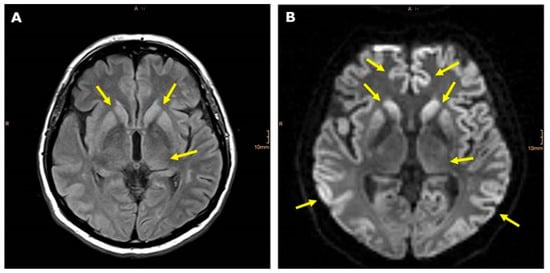

2.1. Clinical Course and Ancillary Findings

2.2. Coma Scale and fMRI